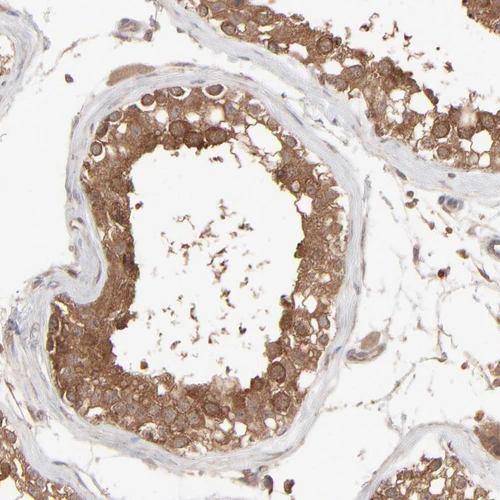

Immunohistochemical staining of human testis shows strong cytoplasmic positivity in cells in seminiferous ducts.